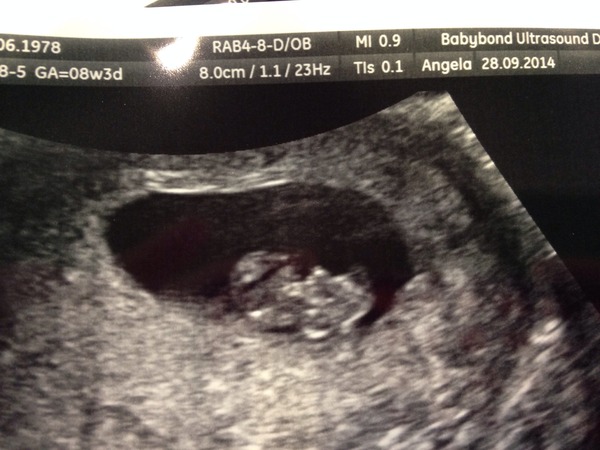

Cup hat how you doing? Sick n stuff? I'm feeling way better now. Had an eight week scan. V reassuring!